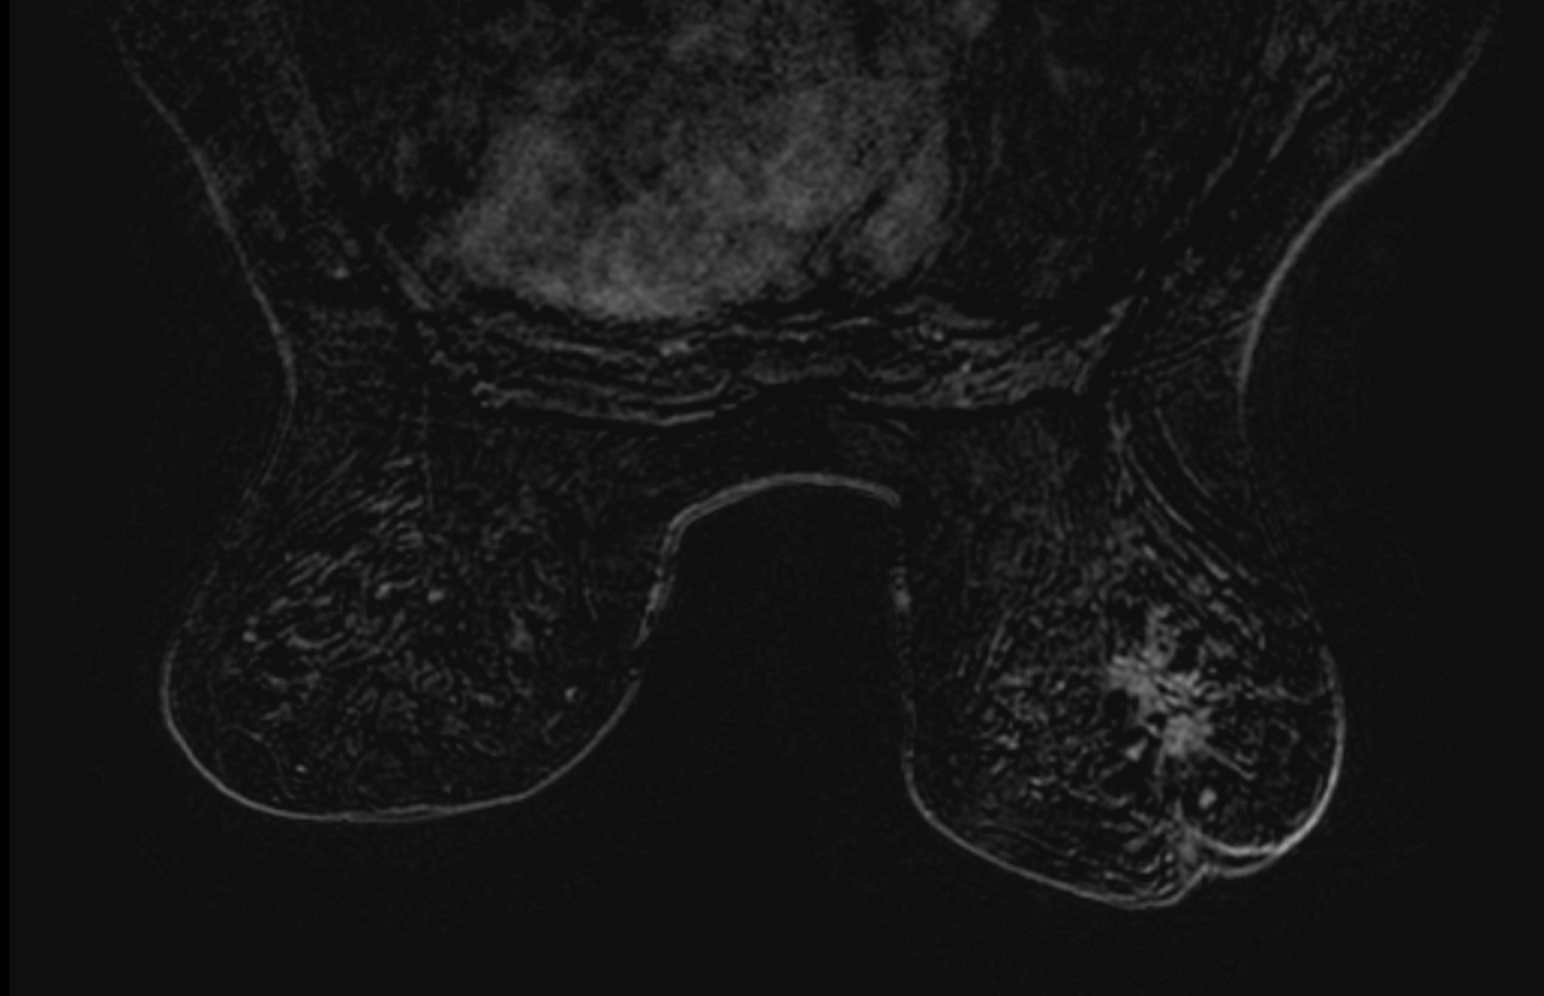

Patiente de 71 ans, masse palpable sein droit négativée 1 mois auparavant, consultation dans un second cabinet pour contre avis.

MammoScreen pointe la masse avec un score 9.

La masse est retrouvée en échographie et mesure 20mm. L’IRM donne une masse volumineuse.

Biopsie : CCI grade 3